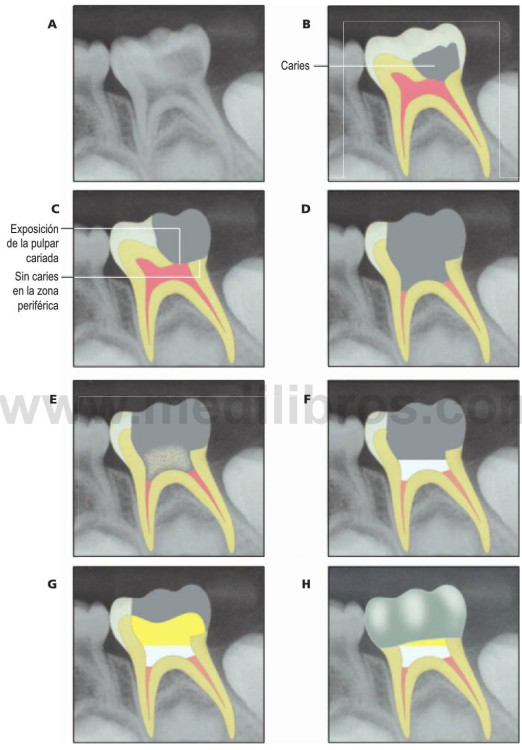

Eliminación de la caries

El diente tratado debe quedar completamente exento de caries antes de llevar a cabo una pulpotomía. La recomendación de eliminar caries desde la periferia a la pulpa no sólo previene la contaminación con restos cariosos del lugar de la pulpotomía sino que también reduce el riesgo de exposición pulpar inadvertida. El acceso a la pulpa coronal requiere una eliminación completa del techo de la cámara pulpar. La amputación de la pulpa coronal requiere un corte limpio en el área del suelo pulpar. Las interdigitaciones residuales de tejido en el lugar de amputación crearán problemas con la hemostasia. La instrumentación rotatoria a alta velocidad con copiosa irrigación de agua en spray favorece el corte óptimo. Si se perfora el suelo de la cámara pulpar, habrá que extraer el diente.

Hemostasia

Debe obtenerse hemostasia en el lugar de la pulpotomía antes de aplicar el agente terapéutico y este efecto se consigue con una irrigación continua y frotando suavemente con bolitas de algodón. Debe producirse en 5 minutos y si no se puede detener la hemorragia, se considera que la inflamación pulpar se ha extendido a las raíces y está asociada a un mal pronóstico que se denomina «signo de sangrado». En estos casos, deben considerarse la pulpectomía o la extracción.

Medicamentos de la pulpa

Una vez obtenida la hemostasia, se aplica el medicamento terapéutico en el lugar de la pulpotomía. Ver más adelante la sección «Agentes terapéuticos utilizados para la pulpotomía en dientes temporales».

A continuación, se recubre el lugar de la pulpotomía con una base terapéutica que suele ser un cemento a base de óxido de zinc eugenol. No obstante, el eugenol en contacto directo con el tejido pulpar provoca una pulpitis crónica, por lo que conviene cambiar a un cemento sin eugenol como base terapéutica. Cuando se utiliza MTA como agente terapéutico, también actuará como base terapéutica. Por último, debe utilizarse un material del núcleo para sellar el diente antes de la restauración final, preferentemente con una restauración de recubrimiento total.

Los primeros textos citados sugirieron que los dientes que debían tener una corona de metal preformada debían someterse también a una pulpotomía rutinaria, tuvieran o no una exposición pulpar cariosa, pero esta postura ya no es defendible dado el éxito previsto del recubrimiento pulpar indirecto.